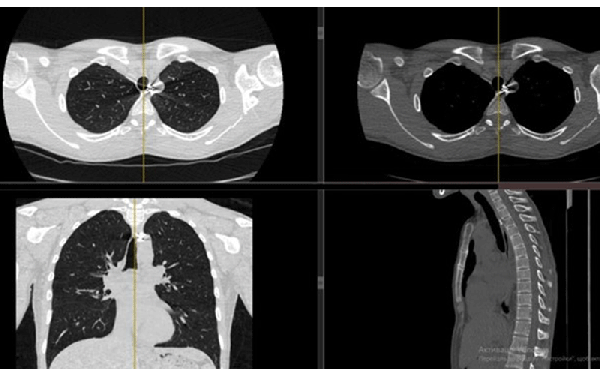

We are not a military hospital, but unfortunately, the number of wounded soldiers is currently so large that military medicine cannot cope with them and numerous civilian hospitals take over the treatment of wounded soldiers. Therefore, among ordinary civilian patients, we examine and treat wounded military personnel. In our hospital, these are mainly acubarotraumas, burns, gunshot wounds of the maxillofacial area, chest, abdominal organs, and of course most of all the trauma extremities.

From the first days we started to provide assistance to wounded civilians and the military from different parts of our country. Our work is to diagnose various injuries of the chest, abdomen, skull, pelvis and especially the limbs. We help thoracic, abdominal and facial surgeons, ophthalmologists, and especially orthopaedists in preoperative and postoperative stages of the treatment.

One of our tasks, as radiologists, has been to find foreign bodies in the people’s arms, legs, abdomen and thoracic wall with help of radiography or ultrasound. We also help in finding traumatic injuries to internal organs. Despite the lack of new equipment, we try to help all our patients as much as possible. Psychological support of patients is also important in our work, which I am doing.

Most examinations of the wounded are carried out in the wards due to the severity of the patients' condition, and X-rays are taken with the help of traditional non-digital machines. We are still waiting for the state CT scan in the hospital, we have only private near the hospital. The MRI machine (0.75 T) has been in use for more than 20 years. Among five stationary X-ray machines, only two are digital, and those without remote access to data for control, comparison. Of the eight ward X-ray machines, only one is digital. Our American colleagues presented it to our hospital. In some departments and operating theaters, there is no US equipment and C-arches for controlling operation procedures.